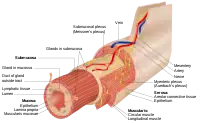

The gastrointestinal wall of the gastrointestinal tract is made up of four layers of specialised tissue. From the inner cavity of the gut (the lumen) outwards, these are:

The mucosa is the innermost layer of the gastrointestinal tract. It surrounds the lumen of the tract and comes into direct contact with digested food (chyme). The mucosa itself is made up of three layers:[1] the epithelium, where most digestive, absorptive and secretory processes occur; the lamina propria, a layer of connective tissue, and the muscularis mucosae, a thin layer of smooth muscle.

The submucosa contains nerves including the submucous plexus (also called Meissner's plexus), blood vessels and elastic fibres with collagen, that stretches with increased capacity but maintains the shape of the intestine.

The muscular layer surrounds the submucosa. It comprises layers of smooth muscle in longitudinal and circular orientation that also helps with continued bowel movements (peristalsis) and the movement of digested material out of and along the gut. In between the two layers of muscle lies the myenteric plexus (also called Auerbach's plexus).

The serosa/adventitia are the final layers. These are made up of loose connective tissue and coated in mucus so as to prevent any friction damage from the intestine rubbing against other tissue. The serosa is present if the tissue is within the peritoneum, and the adventitia if the tissue is retroperitoneal.

General organisation of GI tract The wall of the stomach.